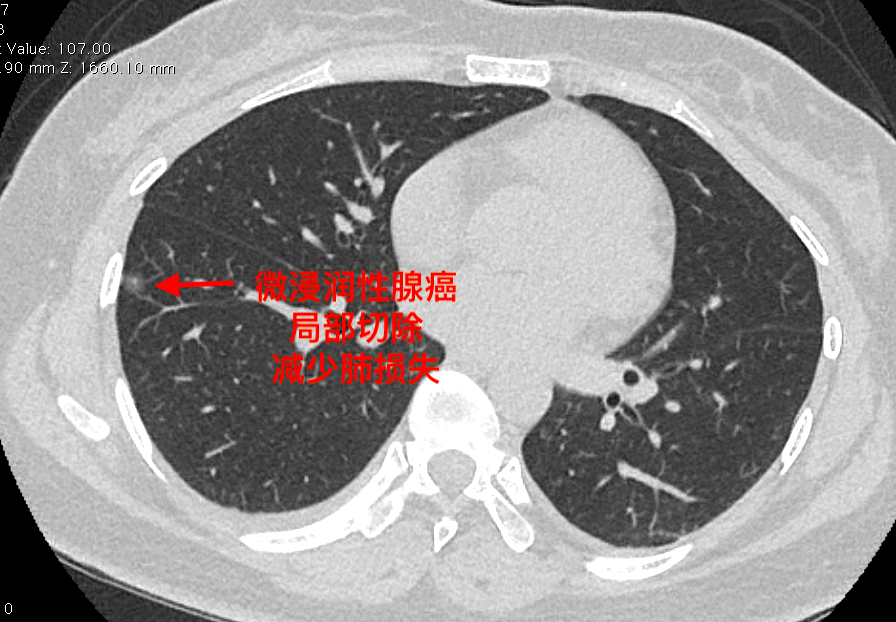

左上肺叶实性结节,不规则,可见毛刺,根据临床经验考虑为肺癌可能性大.